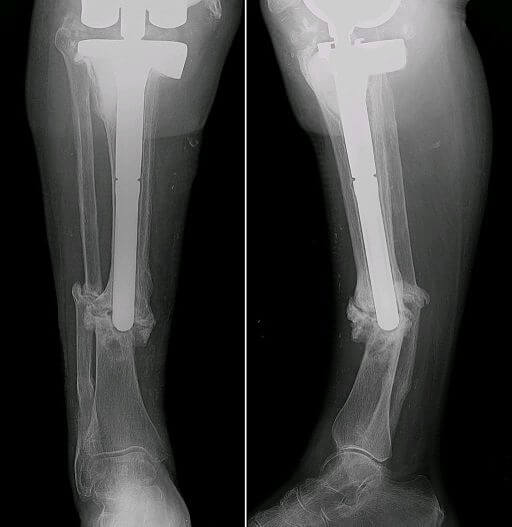

Qualora la frattura non dovesse saldarsi e, quindi, guarire, sarà, ovviamente, opportuno procedere ad un intervento chirurgico volto ad avvicinare i capi ossei, nel quale verranno usati viti e fili di kirshner per stabilizzare la frattura.

Se esiste la necessità di aiutare l’osso a rigenerarsi, è possibile usare degli innesti di osso autologhi (prelievo di piccole quantità dalla cresta iliaca) oppure utilizzare osso preso da donatore (allograft).

Nel caso che una frattura consolidata degenerata in pseudoartrosi sia stata curata chirurgicamente, è comunque necessario assicurarne la completa ed ottimale guarigione con con la fisioterapia fisica, onde d’urto e campi magnetici.